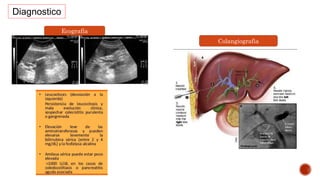

Diagnostico

Colangiografia

Ecografía

Diagnostico  BH  PCR TRANSAMINASAS ECOGRAFIA Centelleografia – acido hidroximinodiacetico